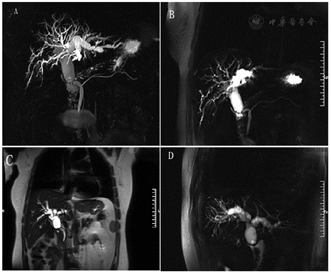

实验室AST: 114 U/L,ALT: 205 U/L,TBIL:141.10μmol/L, DBIL: 125.20μmol/L, IBIL:15.9μmol/L。AFP、CEA、CA125、CA199等肿瘤标志物均正常。腹部超声提示肝内及肝外胆管扩张。CT示胆总管下段占位性病变(图1)。MRCP提示胆总管中段局限性狭窄并肝内外胆管及胆总管上段扩张,不支持典型肿瘤性病变(图2)。ERCP提示胆总管远端正常,导丝无法通过胆总管下段(图3)。

经组织病理学证实,胆总管隔膜由肌纤维层组成,覆盖正常上皮[5]。这与我们的病理结果一致。先天性胆总管隔膜必须与良、恶性肿瘤及假性肿瘤鉴别,避免误诊以及进行更有效的治疗。本例中MRCP及增强CT均没有明确隔膜畸形的诊断,仅病理证实隔膜存在,可能与该病发病率低以及对该病影像特征的认识不足有关。MRCP通过多平面重建可对胆总管腔内隔膜部位、走形进行多角度、全方位的观察,被认为无创诊断胆总管隔膜的最佳方法[5,7]。